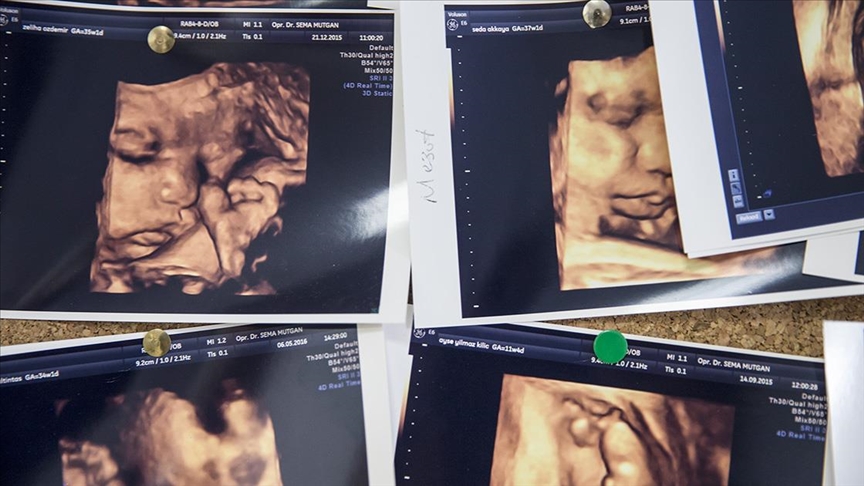

Çoğul gebelik oranları Kovid-19 sonrası dünya genelinde artışa geçti